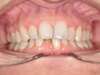

Cas 5 : Description

Absence congénitale des incisives latérales supérieures. Appareils fixes pour créer l’espace nécessaire à la mise en place de facettes en remplacement des latérales.

Après